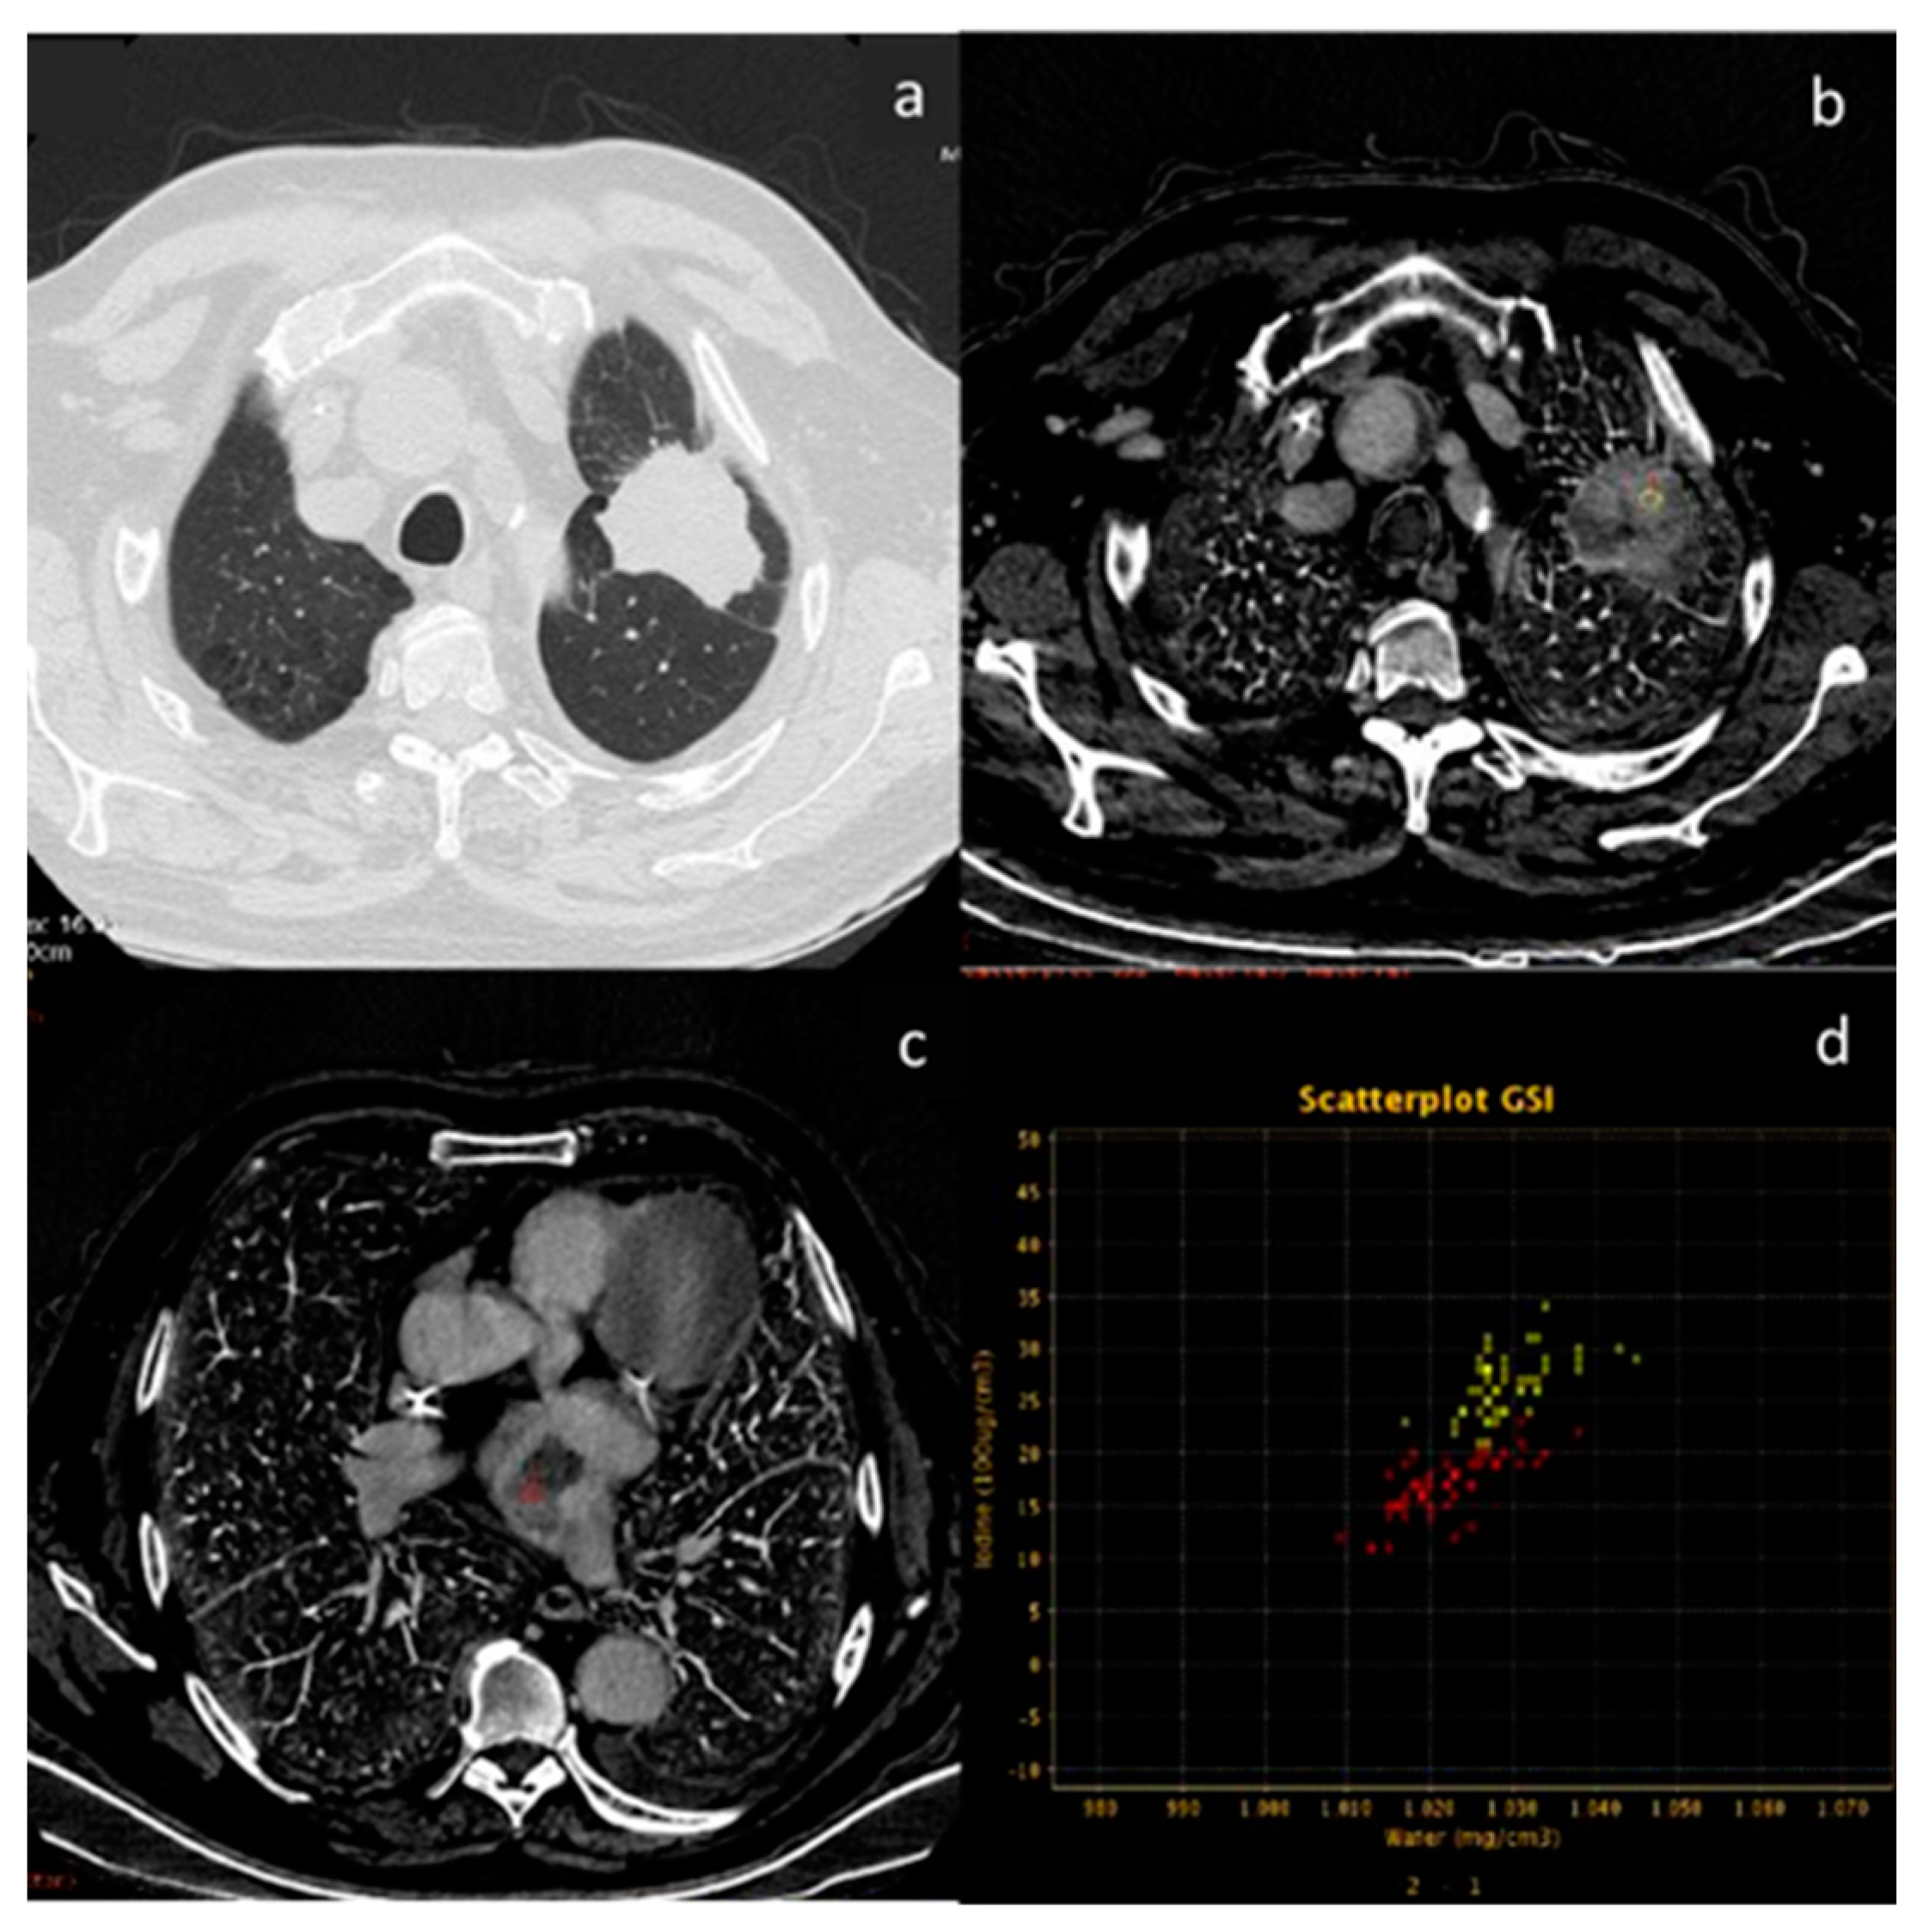

- Volterrani, L.; Gentili, F.; Fausto, A.; Pelini, V.; Megha, T.; Sardanelli, F.; Mazzei, M.A. Dual-Energy CT for Locoregional Staging of Breast Cancer: Preliminary Results. Am. J. Roentgenol. 2020, 214, 707–714. [Google Scholar] [CrossRef] [PubMed]

| Volterrani et al. [57] Retrospective study | Italy | To demonstrate the feasibility of DECT for locoregional staging of breast cancer and differentiation of tumor histotypes | 31 | Discovery CT 750 HD, GE Healthcare No C.I. | DECT is feasible and seems to be a reliable tool for locoregional staging of breast cancer. |

| Moon et al. [58] Retrospective study | South Korea | To evaluate the predictive value of VMI by assessing tumor conspicuity on dual-layer spectral detector CT and correlate tumor conspicuity on VMI with prognostic biomarkers in patients with breast cancer | 64 | IQon Spectral CT, Philips Health System No C.I. | VMI40DEL may be useful in the diagnosis of breast cancers due to higher tumor conspicuity and better enhancement than VMI40ART. VMI40ART may be beneficial for the prediction of poor breast cancer prognoses. |